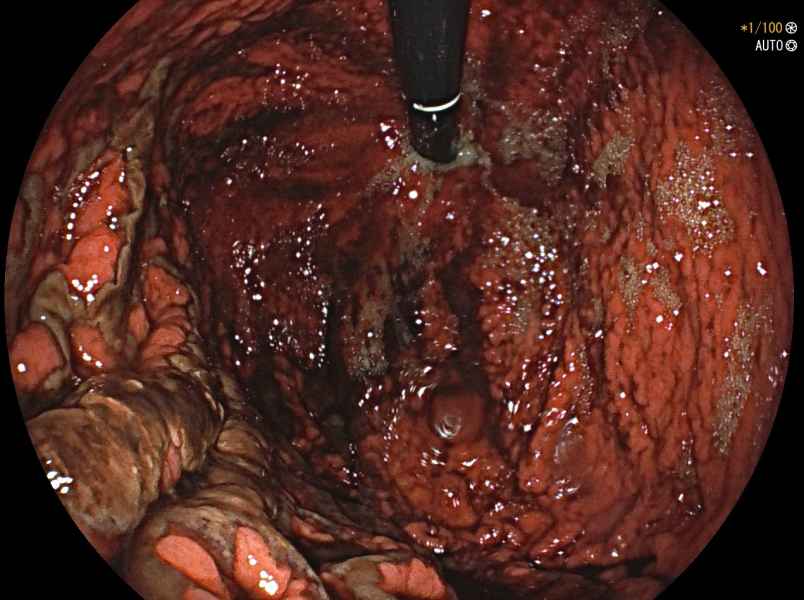

[2º CLASSIFICADO] Giant rectal hemangioma: an uncommon cause of lower gastrointestinal bleeding

Fotografia